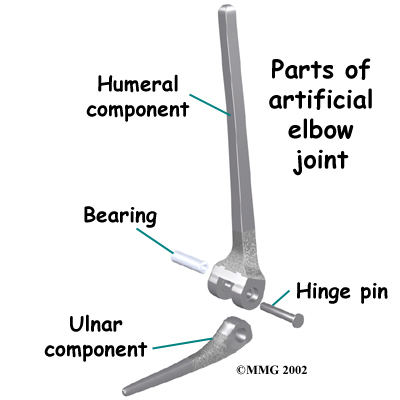

There is more than one kind of artificial elbow joint (also called a prosthesis). The most common types are like a hinge.

Each prosthesis has two parts. The humeral component replaces the lower end of the humerus in the upper arm. The humeral component has a long stem that anchors it into the hollow center of the humerus. The ulnar component replaces the upper end of the ulna in the lower arm. The ulnar component has a shorter metal stem that anchors it into the hollow center of the ulna.

The hinge between the two components is made of metal and plastic. The plastic part of the hinge is tough and slick. It allows the two pieces of the new joint to glide easily against each other as you move your elbow. The hinge allows the elbow to bend and straighten smoothly.